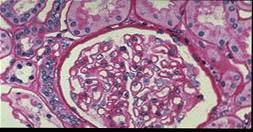

- 单项选择题如图所示,关于这两张病理图片, 下列哪项说法是正确的

A、上图系膜增生,下图正常

B、下图系膜增生,上图正常

C、均正常

D、均系膜增生